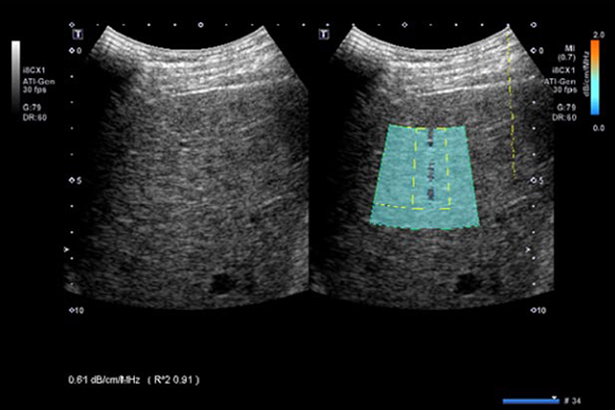

聲衰減成像為脂肪肝、肝纖維化的無創(chuàng)診斷提供定量工具。